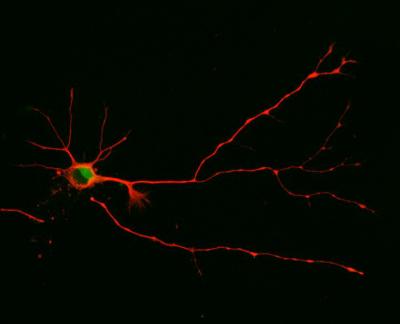

Nerve cells – or neurons – differ from many other cells by their highly asymmetric shape: Vaguely resembling a tree, a neuron has one long, trunk-like extension ending in a tuft of root-like bristles. This is called the axon. From the opposite end of the cell body sprout branch-like structures known as dendrites. By connecting the "branches" of their dendrites to the "root tips" of other neurons' axons, nerve cells form networks, which can be as simple as the few connections involved in the knee-jerk reflex or as complex as those in the human brain.